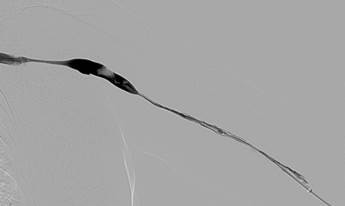

Thrombosed AV Fistula. AVF had previously undergone angioplasty to treat a stenosis in the mid-part.

Fistulogram following two passes with an AngioJet DVX Catheter (no thrombolytics used) and angioplasty of focal stenosis.

Recoil stenosis. A stent-graft was deployed across the stenosis to maintain patency with a good result. The patient dialysed via the fistula the same day.